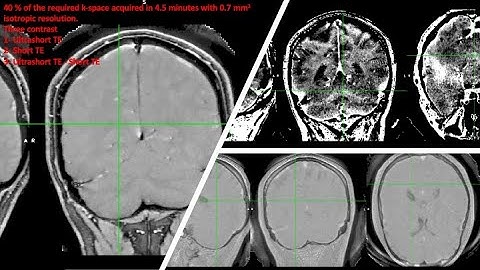

Myelin Imaging Using 3D Dual-echo Ultra-short Echo Time MRI with Rosette k-Space Pattern